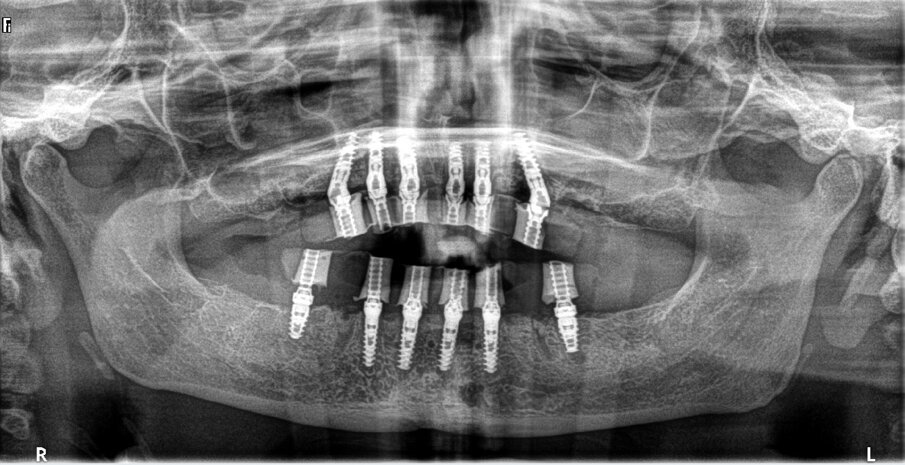

Fig. 16: Post-op panoramic radiograph.

The maxillary provisional restoration was tried in to verify a passive fit over the temporary abutments. Once fit had been confirmed, trimmed dental dam pieces were placed to avoid the restoration (Fig. 11) from locking on during the relining procedure with REBASE III FAST set hard reline material (Tokuyama Dental). After the material had polymerised, the immediate provisional restoration was removed and any access material was removed with the Torque Plus laboratory handpiece (Aseptico) and an acrylic bur (Komet). The same procedures were accomplished in the mandibular arch (Figs. 12–14). Once trimmed and polished, the provisional restorations were seated and tightened with a torque wrench at 15 Ncm (Fig. 15). The access openings were filled in three-quarters of the way with Teflon tape, followed by Cavit filling material (3M ESPE). A postoperative panoramic radiograph was taken immediately after the surgery (Fig. 16).